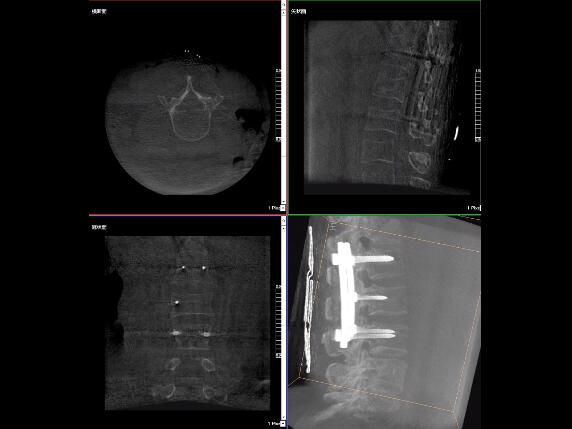

比如,醫生在做PKP(椎體成形術)的時候,或者在置入螺釘的時候,醫生需要在影像上看到螺釘打進去的進針點以及進針的路徑。比如,我們在打腰椎的釘子時需要看到“貓眼”。我們只有把釘子完全打在“貓眼”里面,才能確保釘子打在了椎弓根里,所以對“貓眼”的顯影就非常重要。

“貓眼”指的是椎弓根在正位的投影。

最后我要強調一點,以上我提到的“貓眼”,在二維的X光片上,醫生是靠經驗去判斷釘子是否打在椎弓根里,這個時候如果我們的設備再先進一點,診斷手段再多一點,如果我們能夠把二維的影像轉換為三維的影像,可能就不會完全依賴醫生的經驗。

我們可以在三維的圖像中直觀的看到釘子到底在不在椎弓根里面,這樣可以指導我們準確的進針,指導我們進行一場高質量的手術,可以起到事半功倍的效果,手術會簡單得多,病人的預后也會好得多。